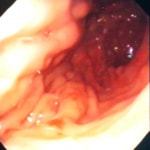

症例:炎症性ポリープ M.ダックス 10歳 オス

主訴:8ヶ月前から便が細くなり、血が混じることがある。その他、元気・食欲等、一般状態は良好。

経過:超音波検査にて直腸壁の肥厚(5㎜)が認められた。また、直腸検査で直腸全周に結節状病変を触知し、出血も確認された。消炎剤、抗生剤、整腸剤による治療への反応が長期的に悪いため、生検も含めた内視鏡検査を実施した。

内視鏡検査:肛門付近の直腸全周に、炎症および出血を伴う結節状病変を多数認めた。

病理検査:直腸の病変は、良性の非腫瘍性病変の一つである“炎症性ポリープ”と診断された。

診断後経過:炎症性ポリープは多発する傾向や腫瘍に転化する可能性があるため、消炎剤、抗生剤、整腸剤による内科療法を継続しながら、現在プルスルー法による外科的摘出術を検討中。

◎炎症性ポリープとは

近年、ミニチュアダックスで好発が知られている良性の腫瘍性の病変です。しばしば多発し、また腫瘍に転化する事があります。